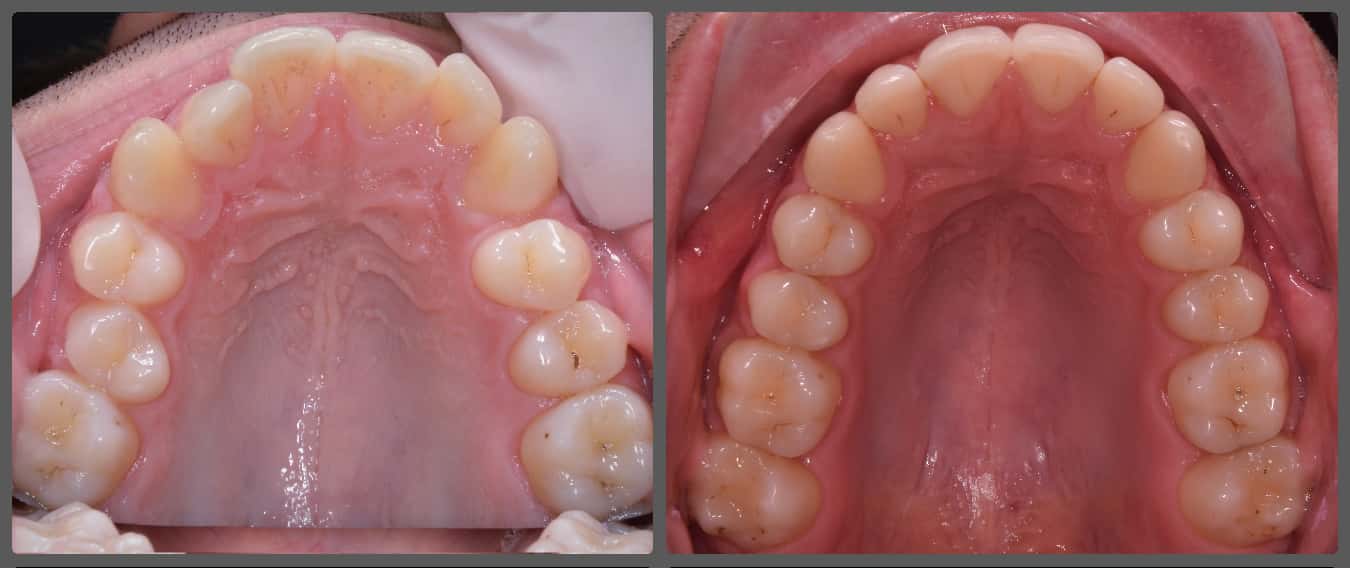

Péter súlyos nyitott harapása miatt szeretett volna fogszabályozót. A kezdeti diagnosztikát követően a nyitott harapáson túl felső fogívszűkületet és enyhe alsó torlódást állapítottam meg. Péternél funkcionális probléma is a felszínre került: nyelvlökéses nyelése volt. A nyelvlökéses kezelés terápiájában logopédus volt segítségünkre, “negatív megerősítésként” pedig a felső metszőfogak belső felszínére ragasztottam nyelvlökés gátló tüskéket. Ilyen esetben a nyitott harapás kezelésénél kulcsfontosságú eldönteni, hogy a harapási eltérés fő oka az állcsontok rendellenes pozíciója, vagy csupán a fogak/fogmedernyúlvány nem megfelelő helyzete. Péter esetében szerencsére főként az utóbbi volt látható, ezáltal nem volt szükség állcsont műtéttel egybekötött fogszabályzó kezelésre. Alsó-felső H4 önligírozó rögzített fogszabályozó készüléket alkalmaztam Péter kezelésénél. A bracketeket az átlagostól “magasabbra”, közelebb az ínyhez ragasztottam. Ez nem csak a mosoly esztétikát javította, hanem a nyitott harapás megoldásában is nagy segítségünkre volt. Péter végig nagyon együttműködő volt, megfelelően hordta az intermaxilláris gumihúzást, és a logopédiai kezelése is szépen haladt, ennek köszönhetően 17 hónap alatt végeztünk a fogszabályzásával! Úgy gondolom, hogy az elért végeredmény kiemelkedően látványos lett!